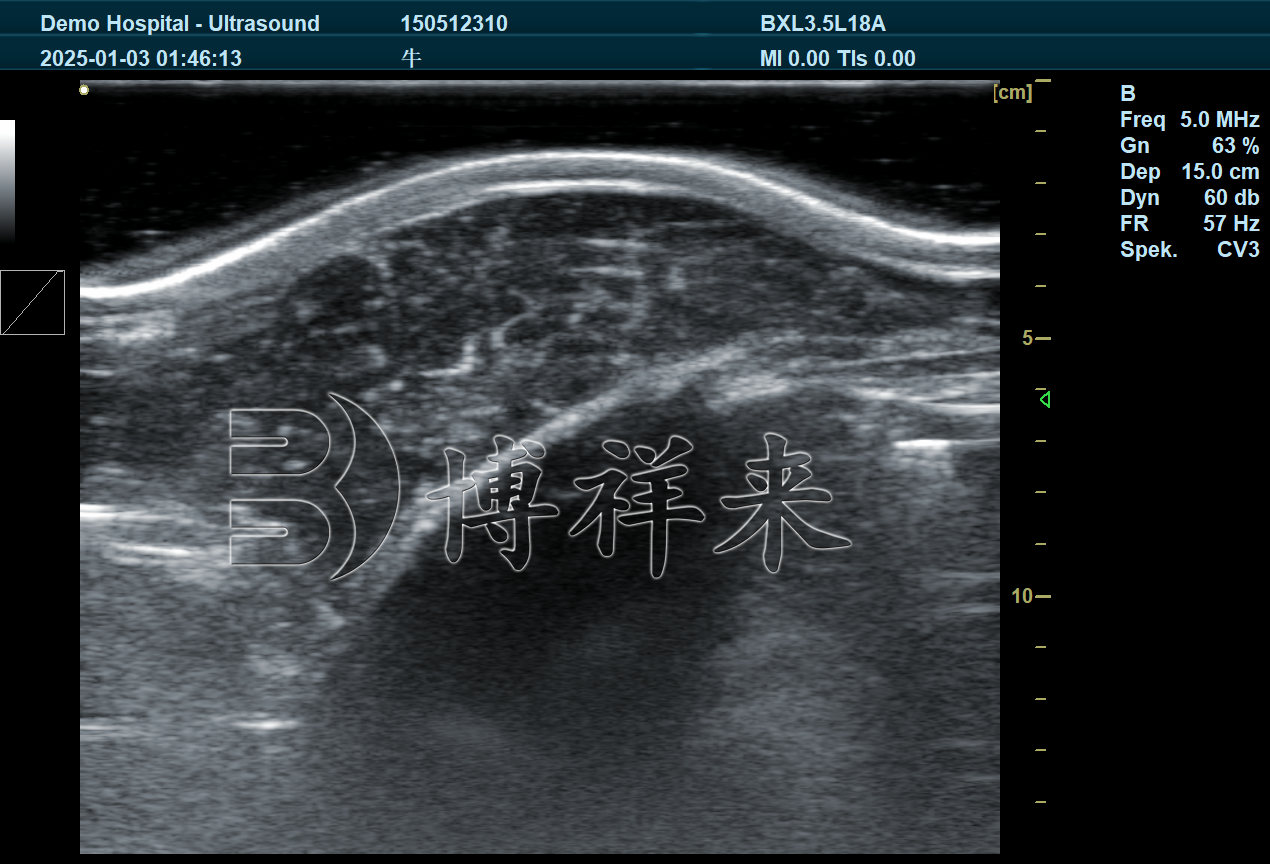

背膘眼肌测定仪是一种利用超声波成像原理的非创伤性检测设备,适用于肉牛育肥期的动态监测。操作时,只需将探头放置在牛只第12–13肋骨交界处,即可实时显示和测量:

背膘厚度

眼肌面积

吉彩网 肌间脂肪纹理(可通过图像分析软件自动评分)

这类设备适合在养殖场现场使用,不会对牛只造成伤害,也不会影响正常生长。

博祥来自主研发的BXL-DB20背膘眼肌测定仪,已在多家肉牛育肥场、育种基地应用,帮助客户实现了肉质可视化管理与品质提升。